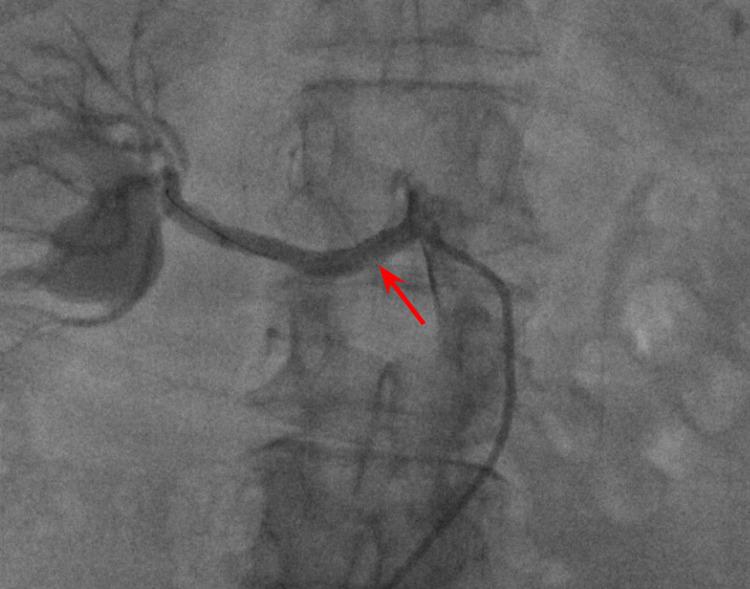

Renal artery stenosis (RAS) is one of the major causes of resistant/malignant hypertension. It can be described as atherosclerotic or non-atherosclerotic. Atherosclerotic RAS comprises almost 90% of all RAS cases and is a prevalent disease of the elderly. Multiple risk factors contribute to atherosclerosis development, which leads to the release of renin and aldosterone, causing resistant/malignant hypertension. Early recognition is prudent but challenging as there are no early clinical signs. We believe that renal resistive index with supportive clinical, laboratory, and imaging modalities can help select revascularization patients.

肾动脉狭窄(RAS)是顽固性/恶性高血压的主要病因之一。它可分为动脉粥样硬化性或非动脉粥样硬化性。动脉粥样硬化性RAS约占所有RAS病例的90%,是一种常见的老年疾病。多种危险因素促成动脉粥样硬化的发展,进而导致肾素和醛固酮的释放,引起顽固性/恶性高血压。由于没有早期临床症状,早期识别虽谨慎但具有挑战性。我们认为,结合支持性的临床、实验室和影像学检查手段的肾阻力指数有助于选择进行血运重建的患者。